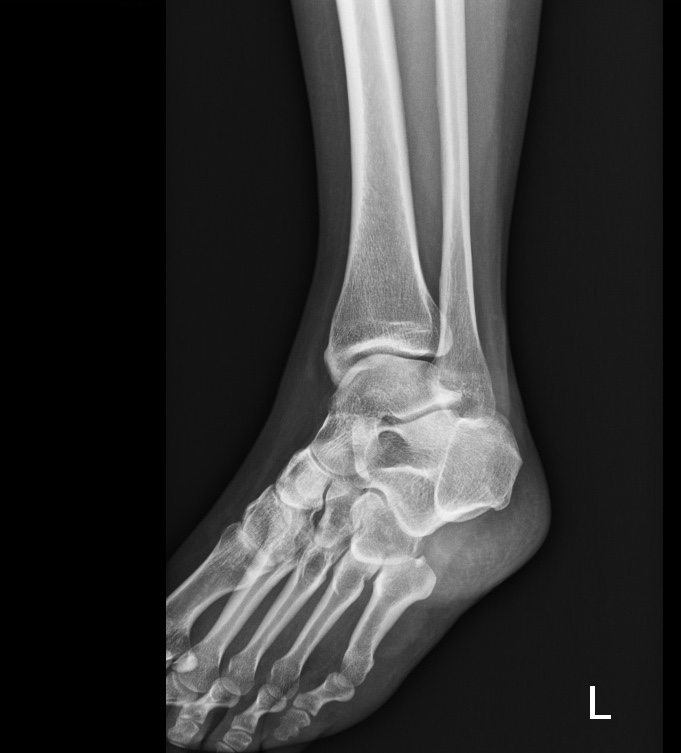

06-20 또 발목염좌 | 또 동생, 친구 웨딩플래너